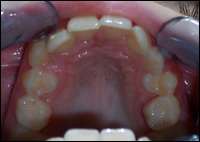

Fig 1 & 2: An 11 year old female presented with a narrow upper and lower dental arches and crowded teeth.